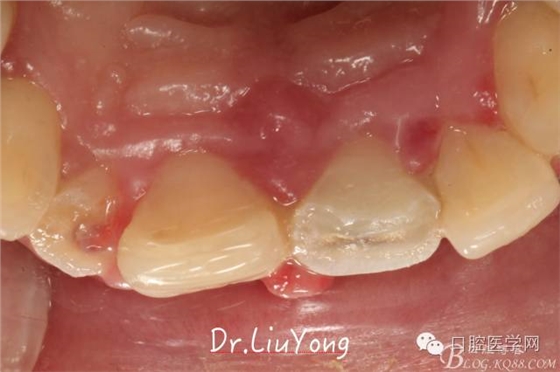

骨塊固定兩周后復(fù)查,如上圖:

松動牙固定一月后拆除,A1-B2無明顯動度,但牙齦紅腫加重,給予全口齦上下潔治刮治術(shù),上藥,醫(yī)囑加強(qiáng)口腔衛(wèi)生,氯己定漱口液含漱。